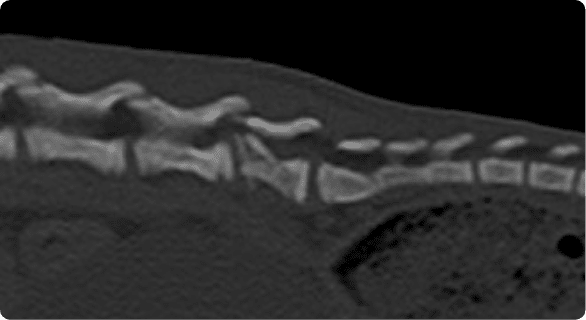

빠른 촬영속도를 통해 마취시간을 최소화 하며, 선명한 3차원 영상을 구현합니다.

종양, 전이평가, 선천적 혈관 기형 등 여러 질환의 조기 발견 및 환자상태를 평가합니다.

골절, 골종양 등